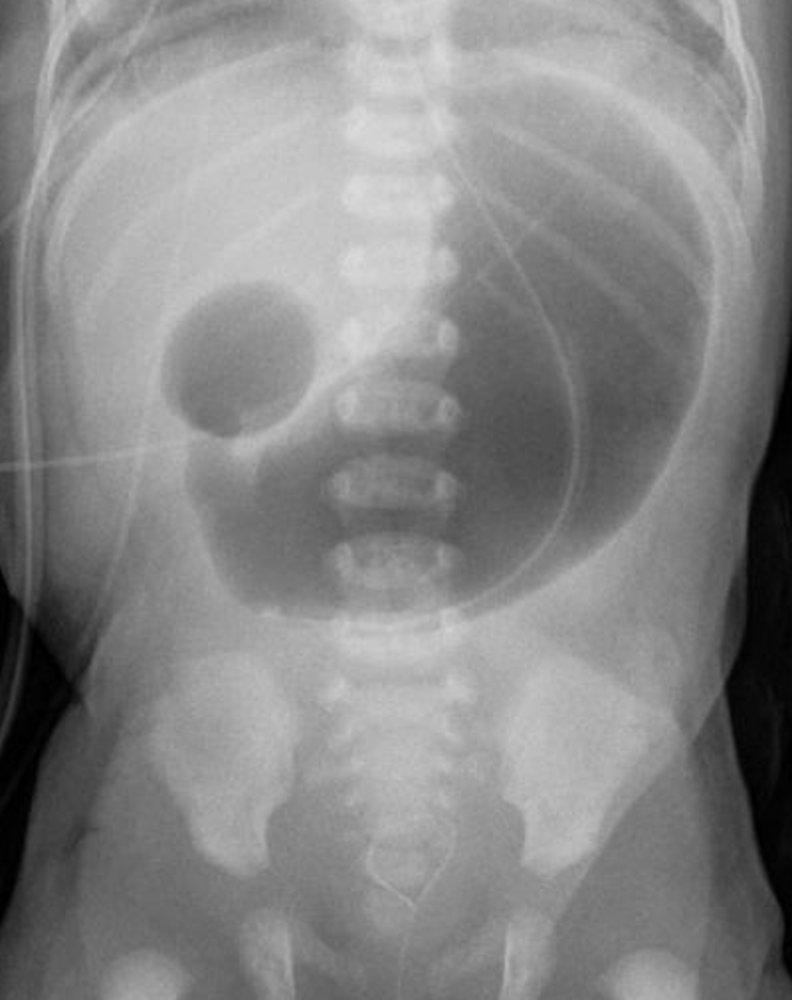

- Abdominal X-ray shows air in the stomach, and proximal duodenum (double-bubble sign) with no distal bowel gas.